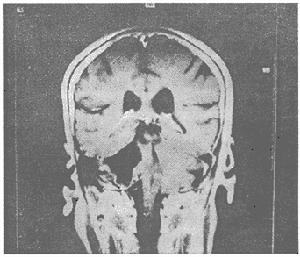

1.顱內壓增高及一般症狀:由於腫瘤生長迅速及周圍腦水腫嚴重,顱內壓增高症狀出現較早而顯著。90%左右病人有頭痛,70%左右有噁心嘔吐,70%以上有視乳頭水腫,30%~40%並有眼底出血,致視力減退者約占20%,約15%有外展神經麻痹,晚期約15%的病人有不同程度的意識障礙,並可有腦疝症狀。 病人一般狀況多較差,有的明顯消瘦。20%左右病人有癲癇發作,多數為局限性發作。由於腫瘤多累及額顳葉且腦水腫範圍較廣泛,亦常有精神症狀。常見的表現為反應遲鈍、表情淡漠等。腦膜轉移主要表現為顱內壓增高和腦膜刺激征,局部體徵很少見。

2.局部症狀:由於腫瘤對腦的損害較重,並且常為多發,局部症狀多顯著,且累及範圍較廣。依腫瘤所在部位產生相應的體徵。40%以上病人有偏癱、約15%有偏側感覺障礙,約10%有失語,5%左右有偏盲。位於小腦者則有眼球震顫、共濟失調等,亦可有後組顱神經症狀。